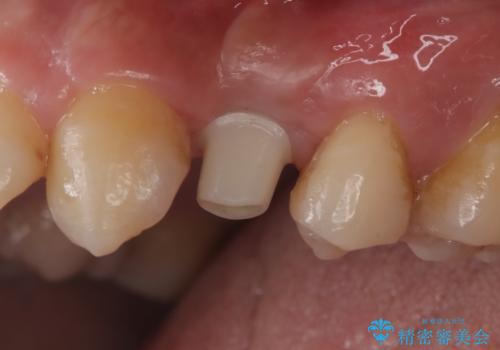

- 440,000円(インプラント体220,000円+カスタムアバットメント110,000円+オールセラミッククラウン110,000円)費用は治療当時の料金となります

長い間虫歯を放置していたため、根っこだけになっている状態でした。このままでは被せ物を被せられないため抜歯を行い治癒を待った後にインプラントを埋入しオールセラミッククラウンで治療を行いました。